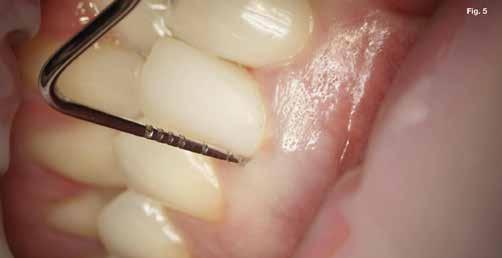

Szépen beállított ideiglenes korona volt jelen, kóros szondázási mélység és szondázási vérzés nélkül. Nem volt jelen sinus tractus (3–5. ábra). Tüneti apikális parodontitis 1. osztály (Von Arx&Cochrane 2001); B osztály (Kim&Kratchman 2005) és korábban elvégzett gyökérkezelés volt a végső diagnózis.

A kezdeti konzultáció során az LL6 nem reagált az Endo-Frost (COLTENE) és az Electric Pulp testerrel végzett érzékenységi vizsgálatokra, és ütögetésre érzékenynek bizonyult. Bukkálisan a lágyrészekhez kapcsolódó fisztulát észleltek, és tapintásra némi érzékenységet, míg a fogak mozgékonysága a normális határokon belül volt. A műtét előtt készült periapikális röntgenfelvételen az LL6 gyökereihez kapcsolódó periradikuláris röntgenfelvételek voltak láthatóak (1. ábra).